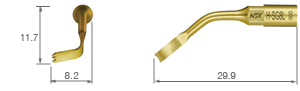

• POWER LEVEL [SURG] 80%

• TiN coating

• 3 teeth ; 0.6 mm thick

• POWER LEVEL [SURG] 80%

• TiN coating

• Dots mark 2 mm from tip end

• Right curved tip*

• 3 teeth ; 0.6 mm thick

* The direction of the tip’s curve is defined by the tip’s anterior view.

• POWER LEVEL [SURG] 80%

• TiN coating

• Dots mark 2 mm from tip end

• Left curved tip*

• 3 teeth ; 0.6 mm thick

* The direction of the tip’s curve is defined by the tip’s anterior view.